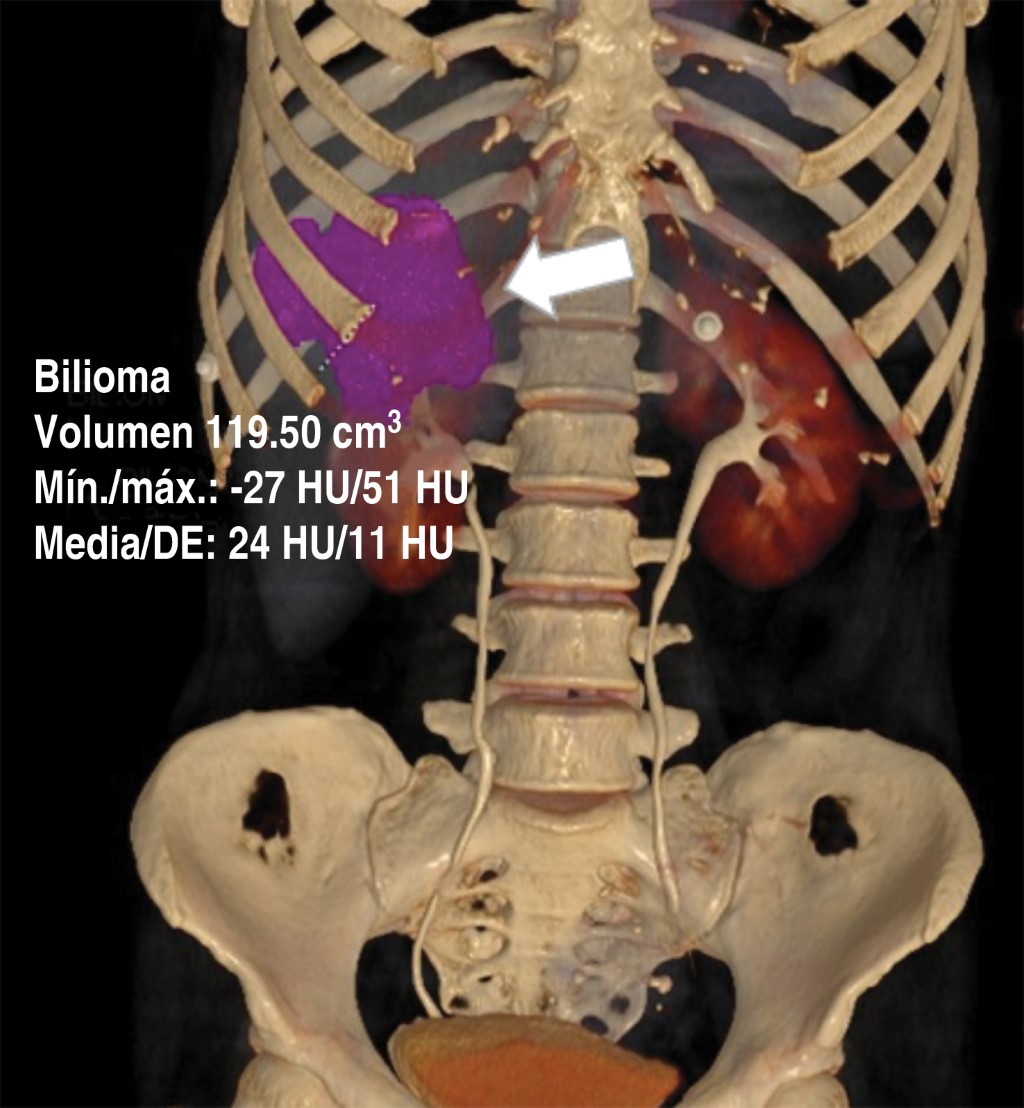

Se trata de paciente femenino de 55 años de edad quien acudió al servicio de urgencias con un cuadro de un mes de evolución caracterizado por dolor abdominal localizado en epigastrio e hipocondrio derecho, irradiado a región interescapular, mismo que fue aumentando, por lo que decidió acudir con facultativo quien inició manejo homeopático; sin embargo, no presentó mejoría, por lo que acudió al servicio de urgencias de nuestra unidad hospitalaria donde se registraron los siguientes signos vitales: TA (tensión arterial) 114/76 mmHg, Fc (frecuencia cardiaca) 124 lpm, Fr (frecuencia respiratoria) 16 rpm, temperatura 36 oC. Al interrogatorio la paciente negó la presencia de fiebre, náusea, vómito o presencia de evacuaciones disminuidas en consistencia. Para su abordaje se solicitaron laboratorios generales, de los cuales destacan la presencia de leucocitosis (12,300 mm3), elevación de fosfatasa alcalina y GGT (315 y 268 U/l respectivamente); se solicitó una tomografía computarizada de abdomen con contraste intravenoso (Figuras 1, 2 y 3) que evidenció la presencia de vesícula biliar con litos en su interior, impactados y ruptura intrahepática, además de un absceso intrahepático en segmentos IV y V (Figura 2).